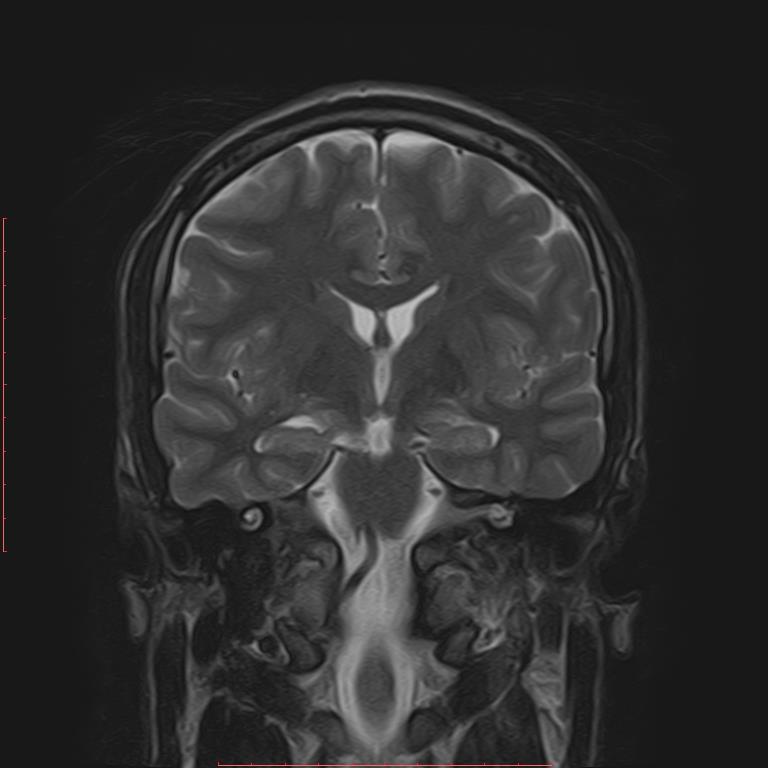

Zdjęcie przedstawia jeden z przekrojów czołowych w badaniu rezonansu magnetycznego głowy. Struktury wskazane strzałkami odpowiadają lokalizacji: